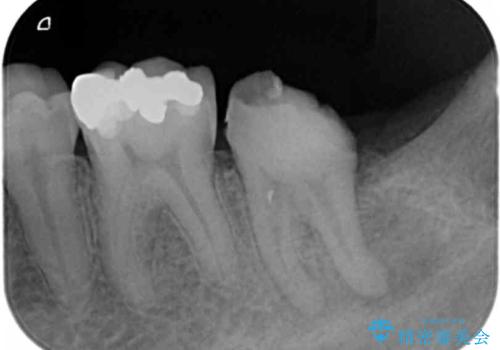

X線写真を撮影すると、根尖部に大きな病変を認め、根管内の感染の除去から治療が必要な状態です。

根管治療→ファイバーコア築盛→セラミッククラウンの作製 を行い痛みを除去・咬合機能の回復を計画します。